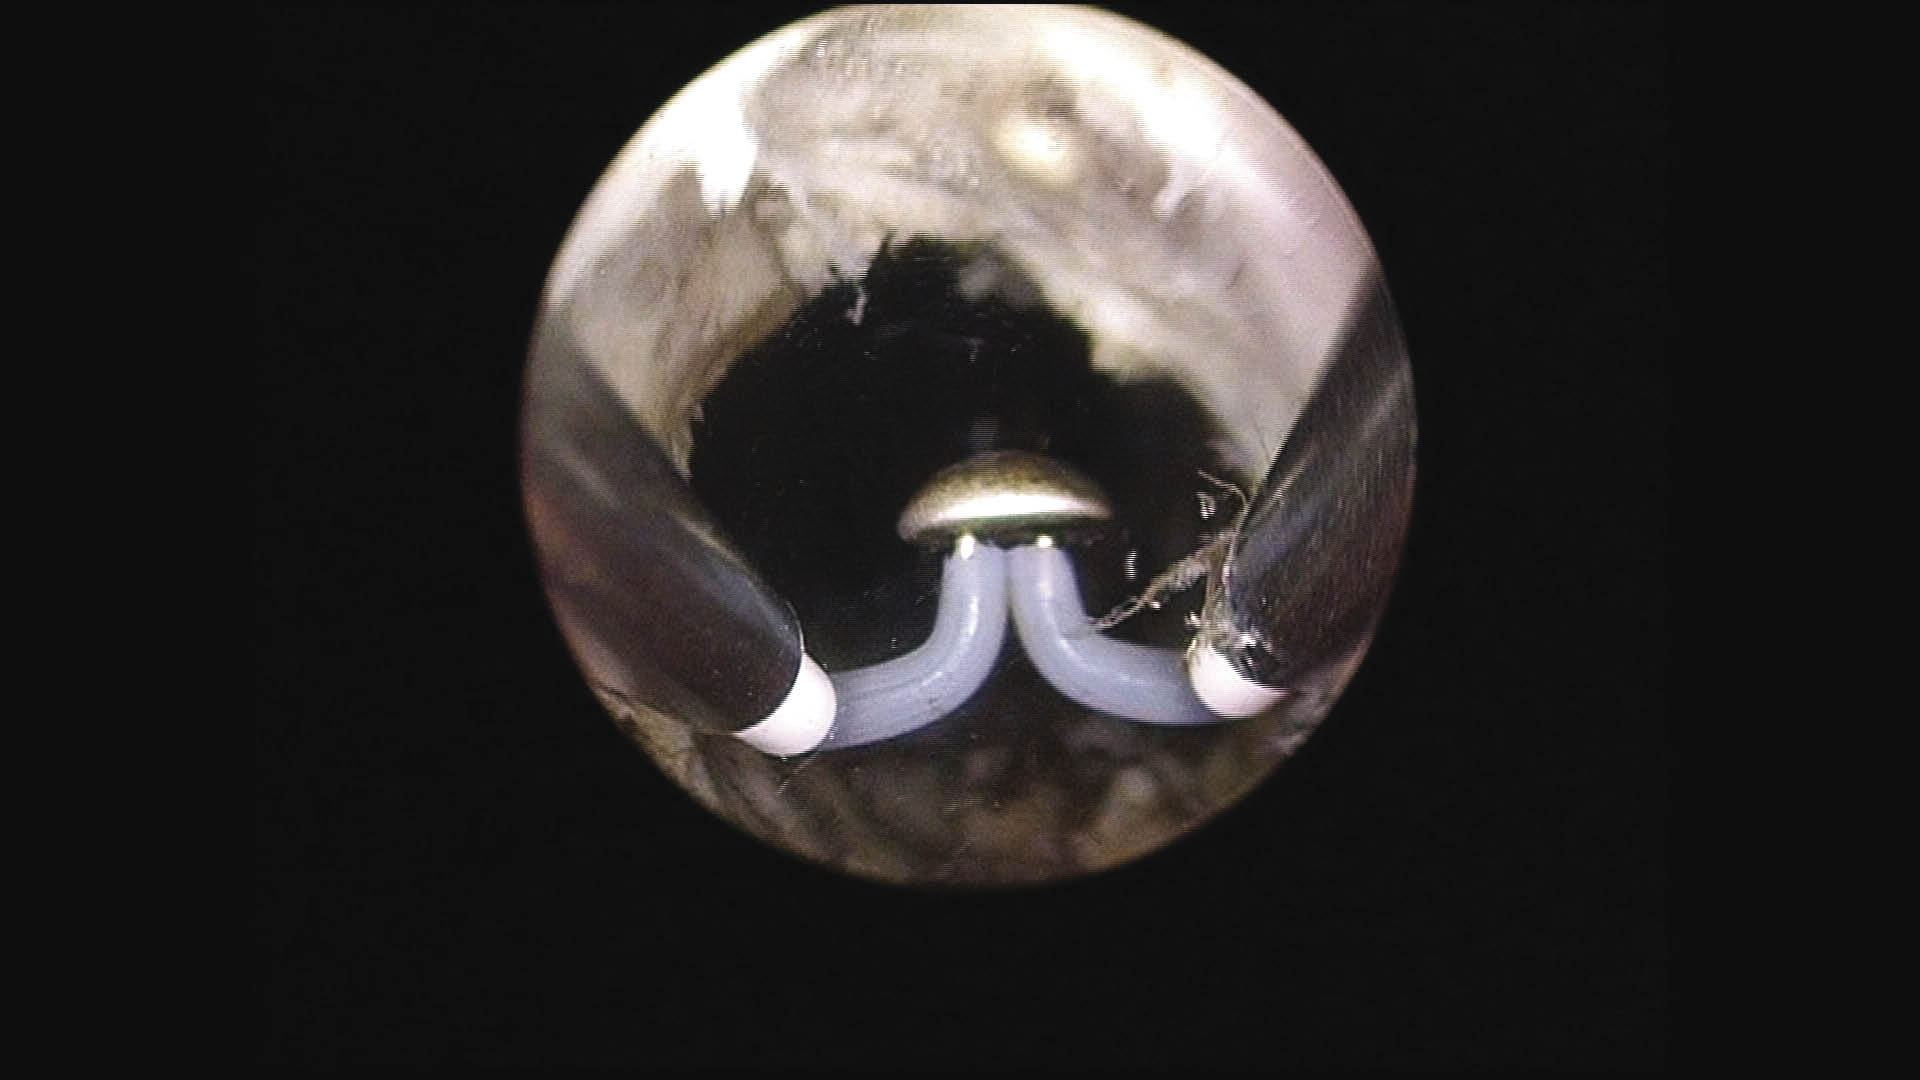

Once the appropriate patient has been worked up and has consented to the procedure, a continuous flow resectoscope is then placed transurethrally using a visual obturator into the prostatic urethra. Inspection of the anatomy is done making sure to visualize the ureteral orifices and verumontanum, Figure 1. The working element is placed into the continuous flow sheath, and vaporization is begun at the bladder neck between the 4 o’clock position and the 8 o’clock position back to the level of the verumontanum. Care is taken to ensure that the verumontanum and the ureteral orifices are not damaged during vaporization.

Figure 1. Start of the case. Image of the untreated prostate.

HOW-DO-IT-Fig1.jpg